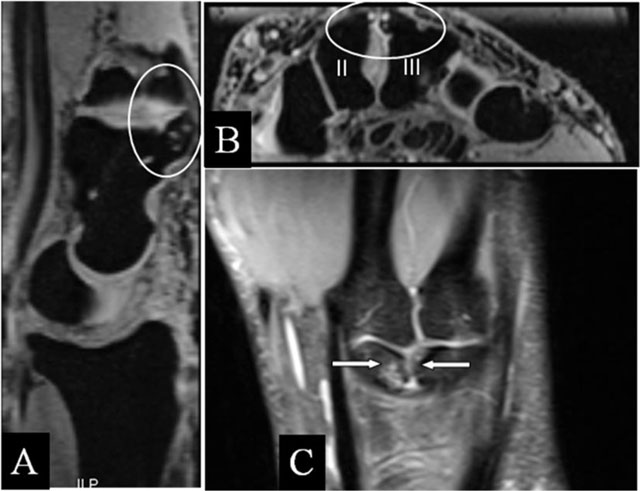

Figure 8

Scapholunar and lunotriquetral abutment. (A) PA plain radiograph; (B) Coronal SE PD-WI FS; (C) Coronal SE T2-WI FS; (D) Coronal 2D-GRE; (E) Coronal SE T2-WI FS; and (F) PA plain radiograph. (A) Widening of the scapholunate joint space on a Schneck I view. (B) Tear of the scapholunate ligament. (C) Juxta-articular subchondral band shaped marrow oedema. (D) Tear of the lunotriquetral ligament. (E) Juxta-articular band shaped kissing marrow oedema. (F) Massive deformation at the triquetral bone (other patient).